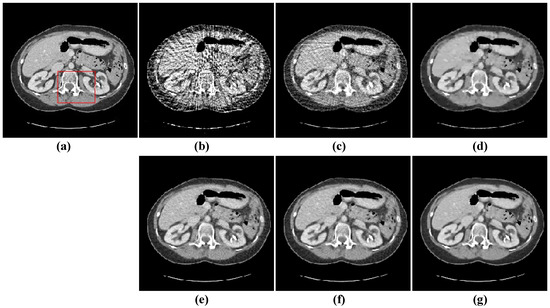

The second image reconstruction experiment is conducted on an abdomen image with more image details to show the feasibility of our algorithm for SVCT reconstruction, as shown in Figure 9. We extracted 80, 64, and 48 views from a full scan and set the parameters as follows: a = 0.5, γ1 = 0.1, and γ2 = 0.06. The reconstructed results using different algorithms are shown in Figure 10, Figure 11 and Figure 12. As can be seen from the figures, our algorithm performs better than other algorithms in preserving small structures and reducing noise. Specifically, FBP reconstruction results contain severe artifacts as displayed in Figure 10b, Figure 11b and Figure 12b. OS-SART reconstruction results also have obvious noise as displayed in Figure 10c, Figure 11c and Figure 12c. TV has a better performance than FBP and OS-SART, but the result has blocky artifacts, as displayed in Figure 10d, Figure 11d and Figure 12d. The PICCS and TVPI-G algorithms have an improvement in image quality, but fine image structures are losing detail and some edge information is blurring, as displayed in Figure 10e,f, Figure 11e,f and Figure 12e,f. As can be observed from Figure 10g, Figure 11g and Figure 12g, the proposed algorithm performs better not only in preserving edge and image details, but also in reducing noise.

Figure 10. 48-views reconstruction results of abdomen image: (a) ground truth, (b) FBP, (c) OS-SART, (d) TV, (e) PICCS, (f) TVPI-G, and (g) NPICCS. The display window is [−150 250] HU.